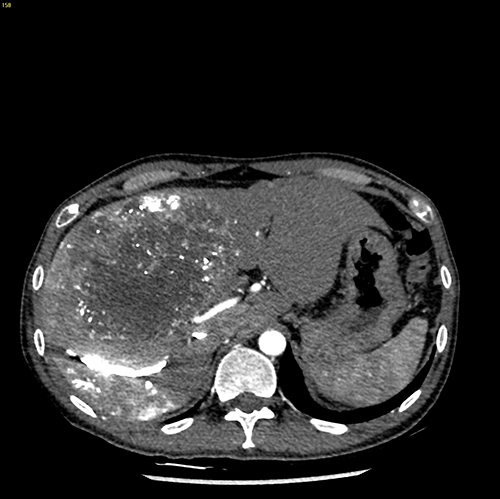

右肝癌---右三肝切除